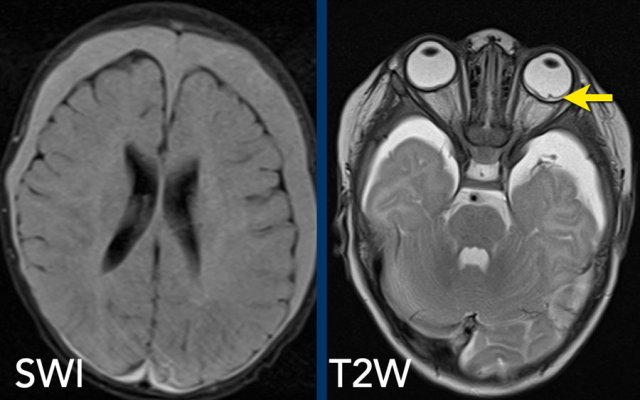

MR

examination is more sensitive in detecting subdural hematomas.

In all

cases we advise to add susceptibility weighted imaging (SWI) sequences to the

imaging protocol.

Images

Subtle subdural hematoma on CT is seen to a better advantage on

T2-weighted MRI and the hemosiderin deposits are evident on the SWI (arrows).

The SWI shows bilateral subdural hematomas in a 3-month-old abused girl.

The T2W-image shows subtle retinal thickening in the right eye

and detached retina on the left.